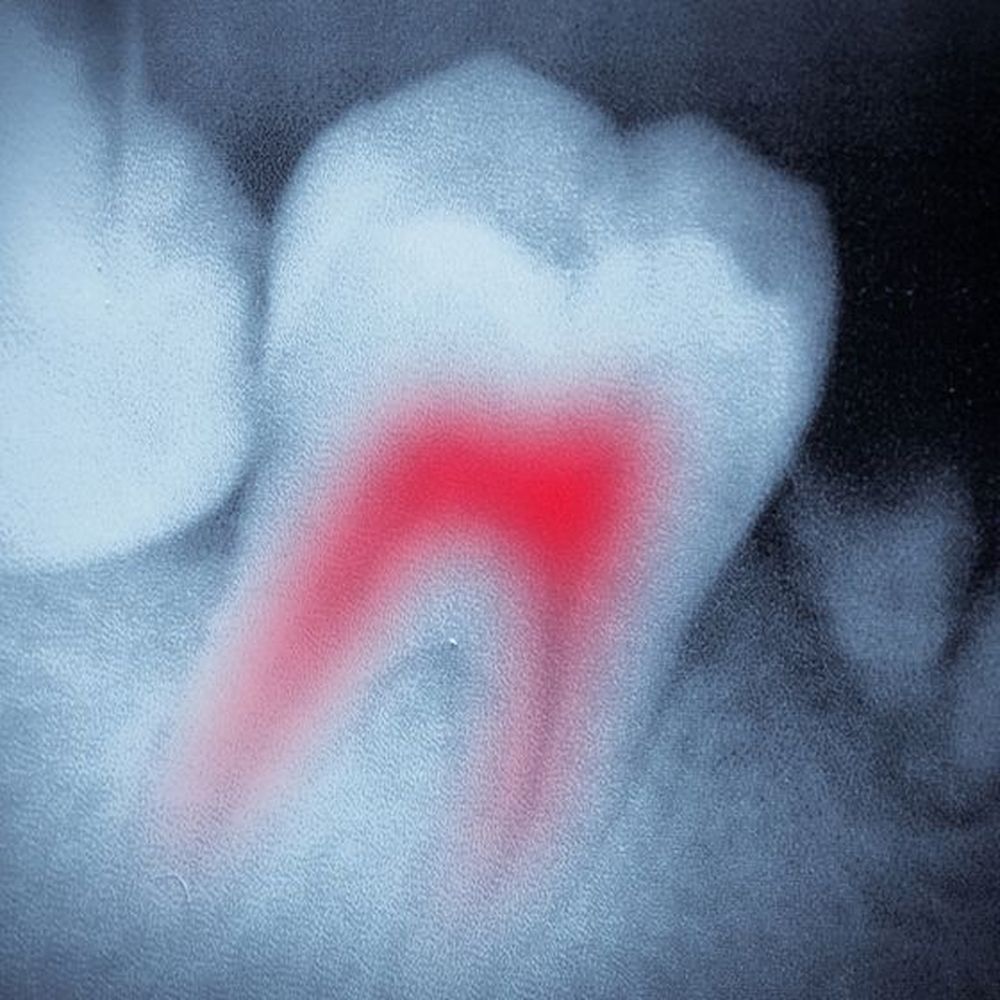

Root Canal Therapy

Our dentists provide root canal therapy to save severely decayed teeth which would otherwise need to be extracted. Root canal therapy eliminates the severe discomfort that occurs when a cavity reaches the nerve of the tooth. In many cases, we can provide a custom-made porcelain crown on the same day as your root canal, protecting the remaining structure from future harm.